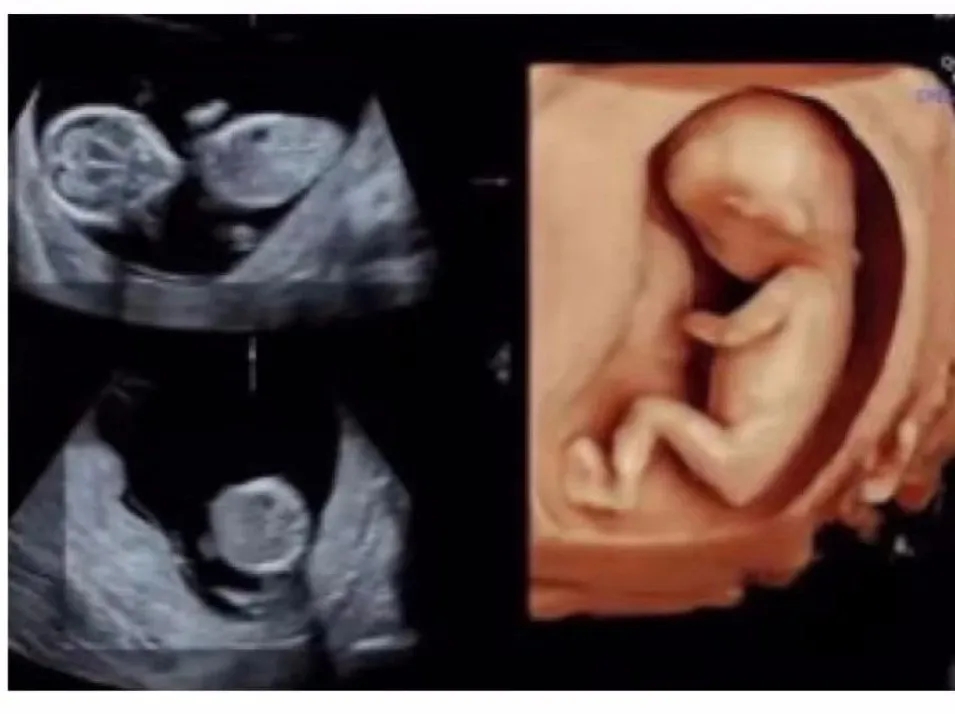

终于,到了李女士万分期待的那一刻,二宝宝就要降生了。在吃完晚饭没多长时间,下午6点钟,李女士感受下面突然一股水流,她觉得不太妙,赶紧联系美琳达客服工作人员,到医院后,经过美琳达住院部医生宋文红和王萍的检查,“李女士是胎膜早破现象,经过系列检查,李女士虽然是瘢痕子宫,但是孩子胎位以及她自身的生产条件是可以试产”。

这个时候,原本计划选择剖宫产的李女士犹豫了,宋文红医生和王萍医生看出李女士犹豫继续劝解“这次检查没有你在生大宝时候出现的羊水少等现象,孩子体重预估是3200克,胎头衔接也很好,作为医生是非常鼓励你试产”,听完之后让李女士有了顺产的信心,与家人商量过后决定选择试产,头一回试产,李女士稍有些紧张,也有很多的疑问,一直在监护她产程情况的宋文红医生和王萍医生都一一耐心地为她解答。而这次的小主人公二宝也是相当努力配合妈妈顺产的决定,晚上9点45分,李女士宫缩频率每2分钟一次,随即李女士被送往产房。